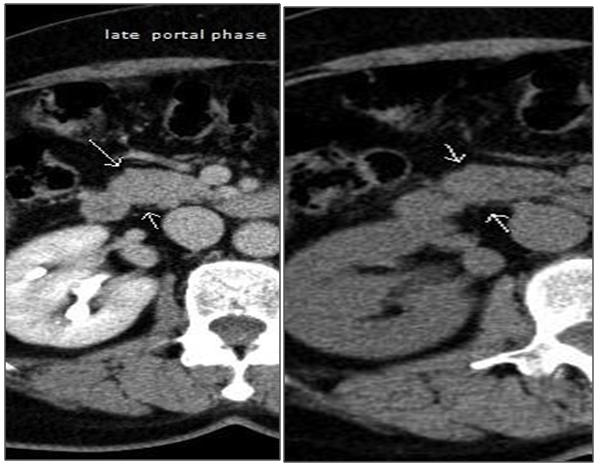

1. Ultrasound and a CT scan with contrast, which showed a single oval nodule with 17x13mm in relation to the duodenal part of the head of the pancreas with rapid clearance of the contrast, unidentifiable in portal phase or late acquisitions (Figure 2A-D).

A/B. Arterial phase. C/D. Early and late portal phase.

Figure 2 Computed tomography with contrast.